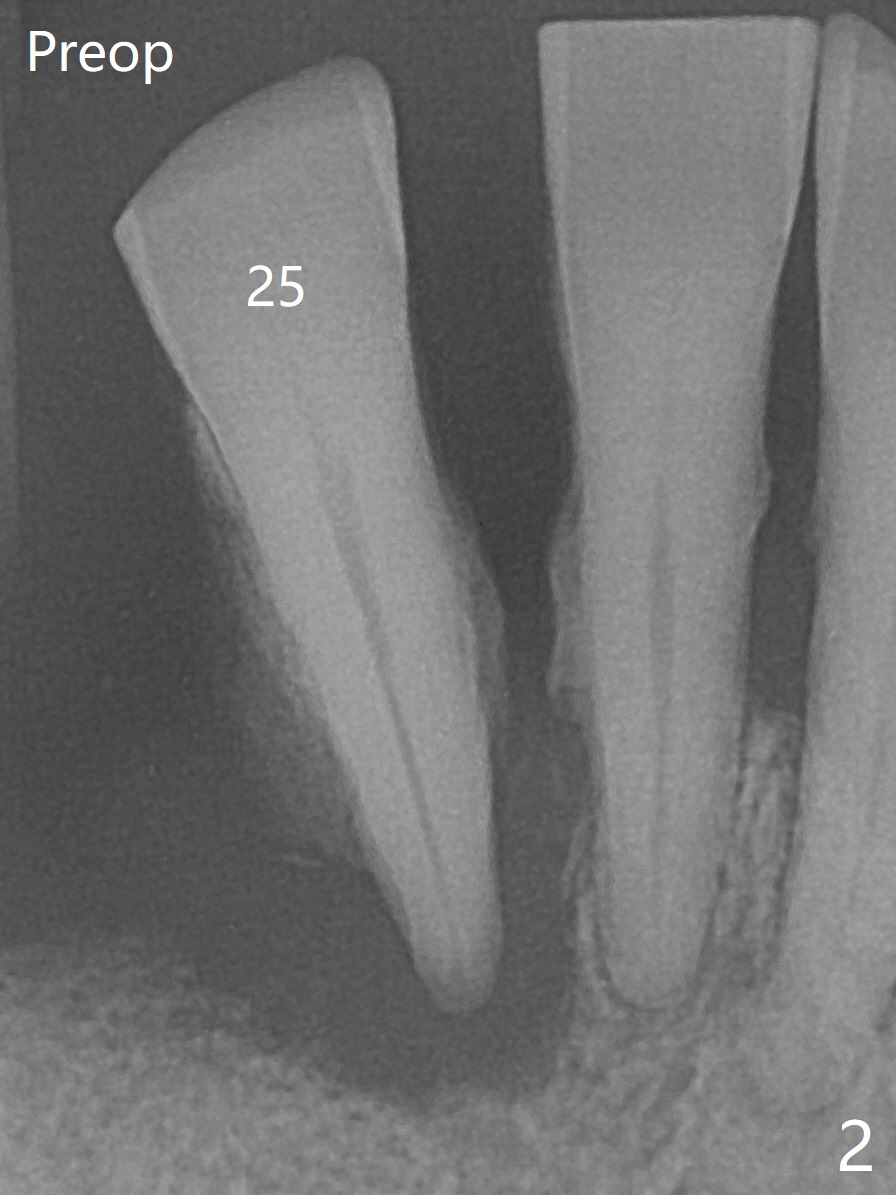

The 58-year-old man returns for #25 extraction while the redo implant at #12 is osteointegrating (Fig.1-3). After discussion, he agrees with socket preservation with 8x8 mm BioXclude (Fig.4 * (4-0 PGA)) and Vanilla graft (Fig.5 *). The socket is healing 6 days postop (Fig.6).